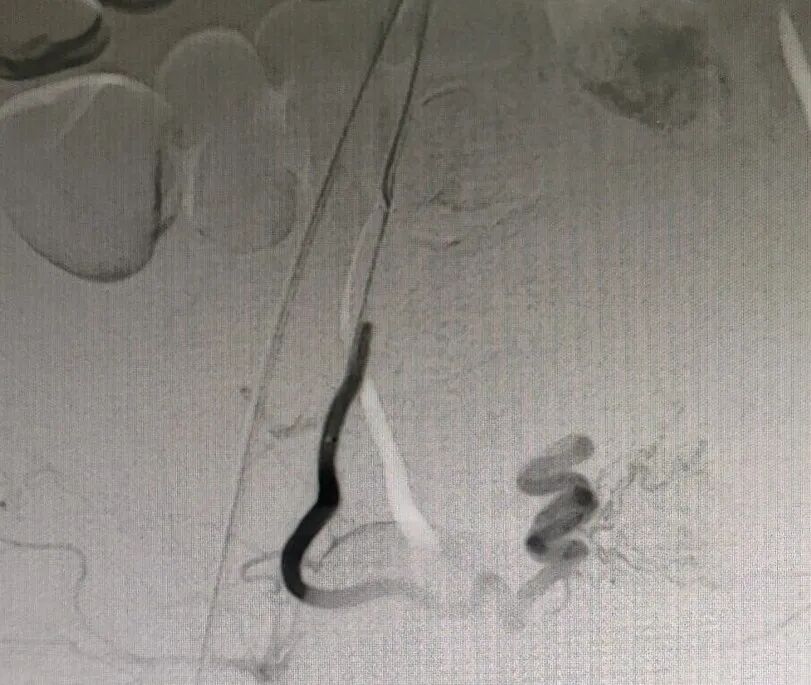

宫腔镜术前影像

图片